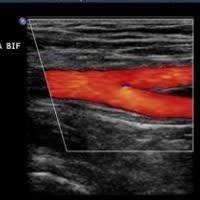

Vascular Services

Allow our dedicated team to put you at ease, while we boast about having top of the range equipment and overqualified staff. Outstanding patient care comes as standard here at NumiScan Basingstoke.